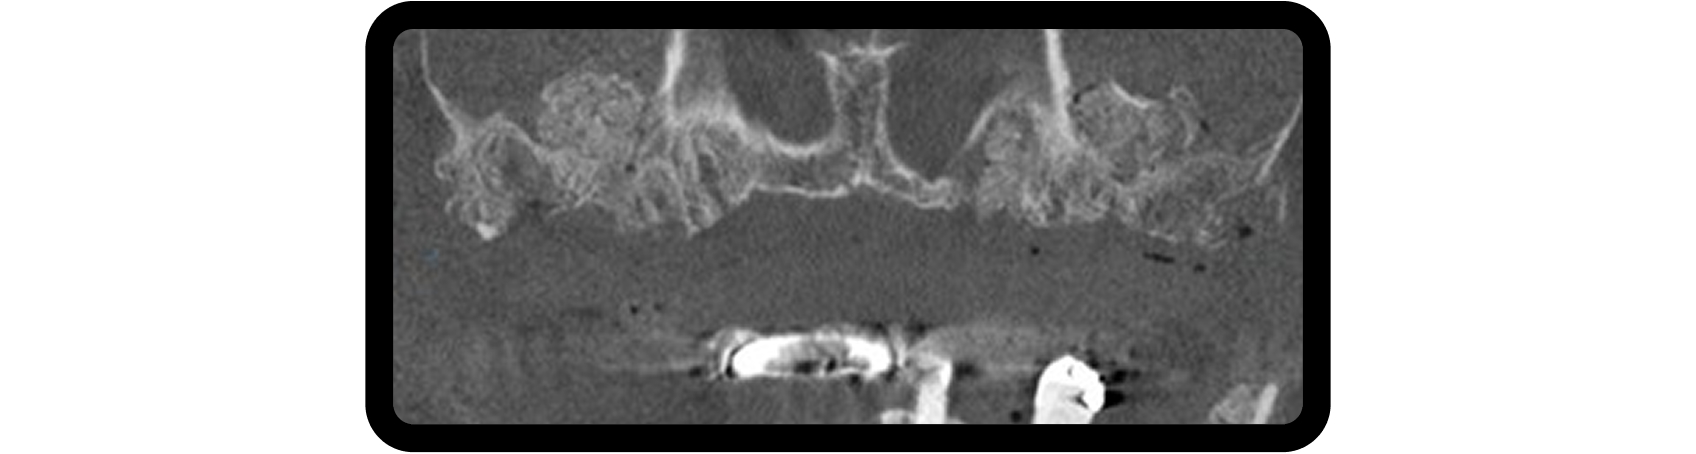

Bilateral sinus augmentation was required to support a six-implant, screw-retained zirconia restoration. A CBCT scan revealed radiolucencies in both maxillary sinuses, prompting referral to an ENT specialist before proceeding (Fig. 4).

Following ENT clearance, lateral window sinus augmentation was performed, with additional grafting in areas affected by periodontal disease (Fig. 5). After six months of healing, six implants were placed to support the planned restoration.